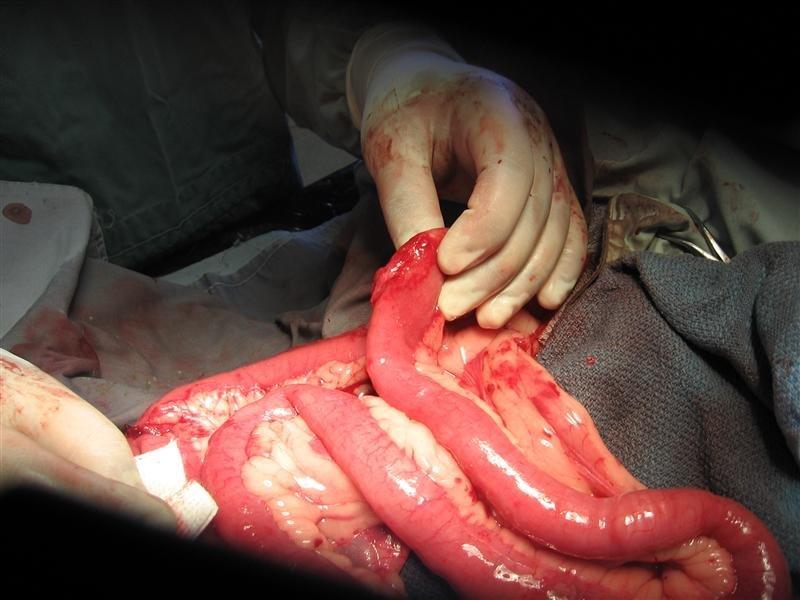

BHRR’s Barkley is healing just wonderfully from his obstruction surgery on April 1st and we continue to thank everyone who has assisted him to date with his BEGGING FOR BARKLEY Fundraiser! I am adding 2 pictures below from April 10th, 2010 and I have so many yet to put together for his slideshow. His sutures were subcutaneous yet you can see how well his incision is looking! Tonight, BHRR’s Barkley is going to help make a TON of homemade cinnamon buns; so that I can bring them into the Hospital with me tomorrow to THANK all the great staff that I work with that pulled together to save his life. It cannot be said enough, what a miracle story Barkley is! He could really use some more financial support to finish paying off his extensive Vet/Rehab Bills and on behalf of BHRR’s Barkley, I humbly thank everyone in advance for your consideration.

BHRR’s Barkley (2.5+) – April 10th, 2010

Since you have now seen the inside of BHRR’s Barkley, let me informally introduce you to the outside of BHRR’s ‘Honourary’ Great Dane, BHRR’s Barkley, the newest addition to BHRR! His coat is really dry, flaky plus dull and he needs a lot more muscle toning BUT he is one gorgeous boy. I cannot wait to see how he looks in a few weeks time! Please consider helping BHRR’s Barkley by donating to his “BEGGING FOR BARKLEY” Fundraiser.

BHRR’s Barkley(2.5+ years of age) – April 1st – post – op at BHRR with Sean & BHRR’s Barkley – April 2nd – 1st day post-op